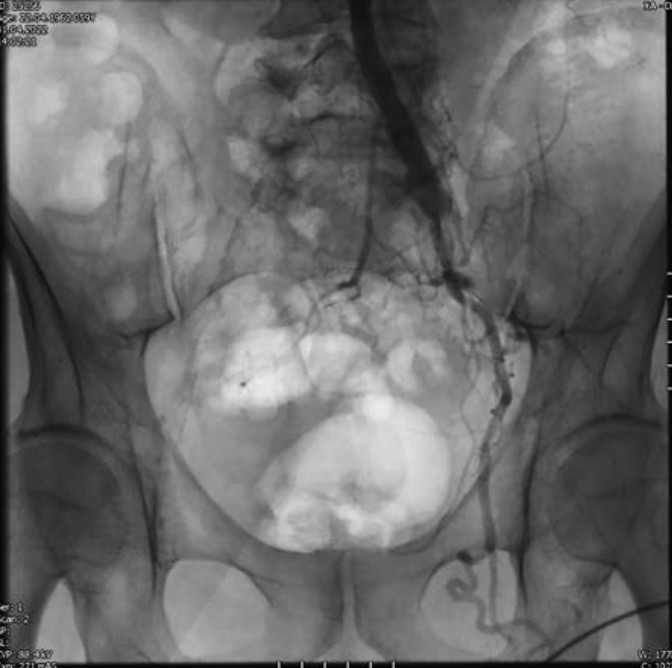

При мультиспиральной компьютерной томографии (МСКТ) с внутривенным контрастированием были выявлены: атеросклеротическое поражение аорты и ее ветвей, окклюзия правой общей и обеих наружных подвздошных артерий (рис. 1).

Рис. 1. 3D-реконструкция МСКТ с внутривенным контрастированием до оперативного вмешательства.